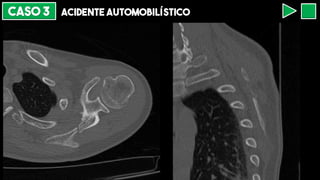

CASO 3 ACIDENTE AUTOMOBILÍSTICO

FRATURA ESTERNAL